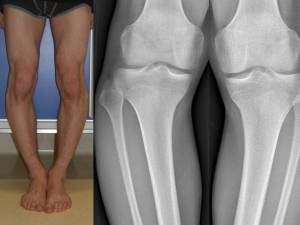

Consiste in una angolazione a vertice esterno dell’asse femoro-tibiale, che realizza, se bilaterale, la tipica deformità “a O” o “a parentesi” (fig 1).

- Fig. 1: ginocchia vare

Il varismo può essere femorale, tibiale o misto. Quando è tibiale si accompagna spesso ad un certo grado di intratorsione. La valutazione clinica può essere fatta misurando, con il paziente dapprima supino e poi in piedi, la distanza massima fra le superfici interne dei due condili femorali o tibiali (DIC = distanza inter condilica, fig 2).